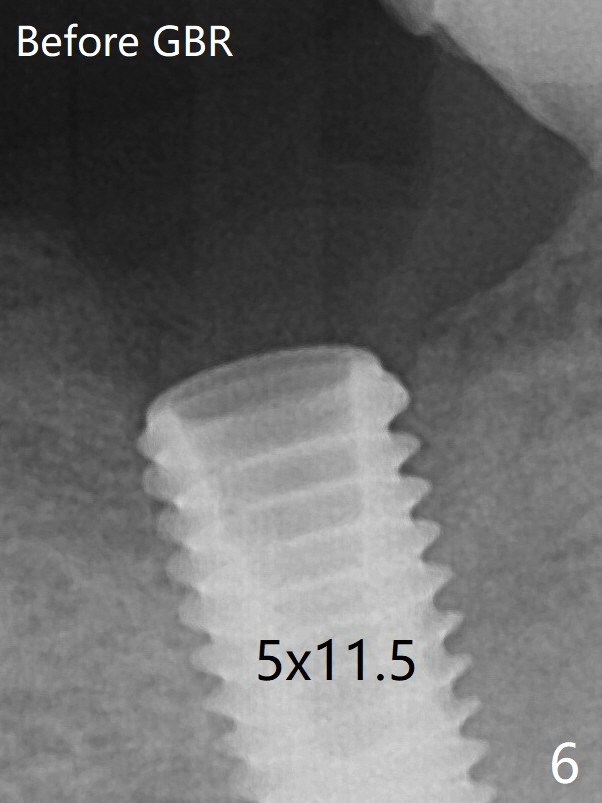

Note radiolucency around the implant (5x11.5 mm) before GBR (Fig.6). There is bone formation coronal to the implant 4 months postop (Fig.8 *), which is removed for uncover.